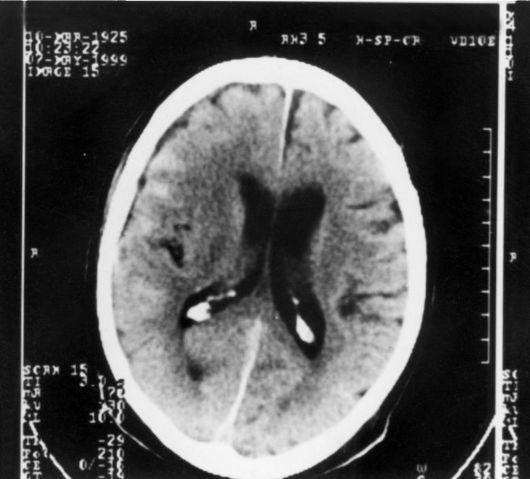

Субарахноидальное пространство зрительных нервов